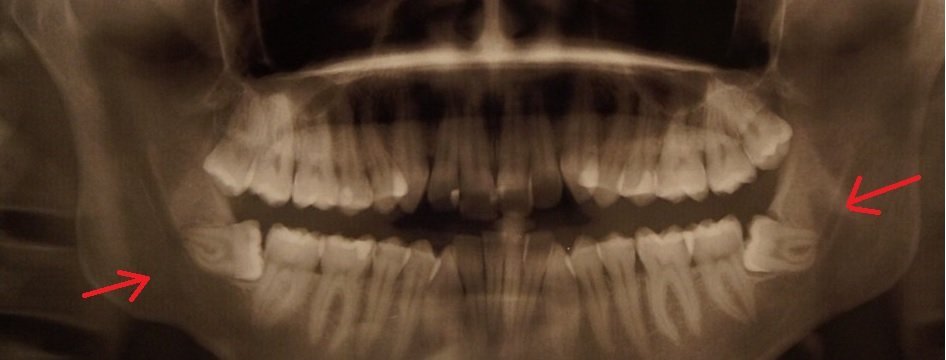

Пикрелейтед пиздец.

Вот вам даже снимок.

С моим зубом проделывали пикрелейтед, сняли временную пломбу, вынули лекарство, пробурили в зубе пещеру, удалили сосудисто-нервный пучок, устроили deep penetration прочистив каналы и потом всё это запломбировали.